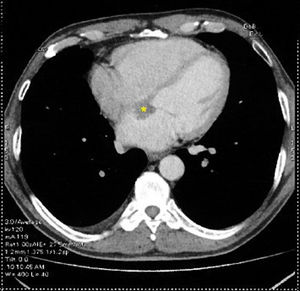

A 57-year-old man was referred to the hospital for evaluation of a right hilar lung mass discovered on a chest X-ray performed because of a persistent cough, increasing effort dyspnea and deterioration of the general condition. He has no medical history and had smoked 35 packs a year. On the admission, physical examination showed a slow heart rate at 40 beats per minute. The electrocardiogram showed a complete atrioventricular block. On echocardiography, a 26×17mm mass was noted in the basal area of the atrial septum without interfering with the mitral valve function (Fig. 1). A thoracic computed tomography (CT) scan revealed a right pulmonary hilum mass with mediastinal and peritoneal lymphadenopathy, adrenal metastasis, and a low-density mass located on the interatrial septum (Fig. 2). Fiberoptic bronchoscopy showed stenosis with mucosal tumor infiltration in the right upper lobe bronchus. The bronchial biopsy revealed a moderately differentiated adenocarcinoma. Based on these findings, the atrioventricular block was associated with interatrial septum metastasis of the lung adenocarcinoma. A pacemaker was implanted and pemetrexed platinum chemotherapy was started.

Myocardial metastases from lung cancer are uncommon. Electrocardiographic abnormalities in include arrhythmia, conduction disturbances and complete atrioventricular blocks.1 Echocardiography is the best non invasive imaging technique for cardiac tumors detection. Cardiac magnetic resonance imaging (MRI), used to determine tumor morphology and to predict malignancy, has higher temporal resolution and further tissue characterization than cardiac computed tomography (CT). CT is an alternative to cardiac MRI and echocardiography.2